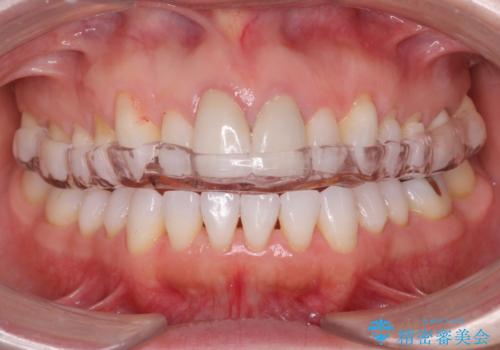

歯を保護するためのナイトガードを装着していきます。

- ナイトガード 33,000円費用は治療当時の料金となります

厚みのあるナイトガードを調整することで、夜間の歯ぎしりにより歯にかかる強い力を分散させることができます。